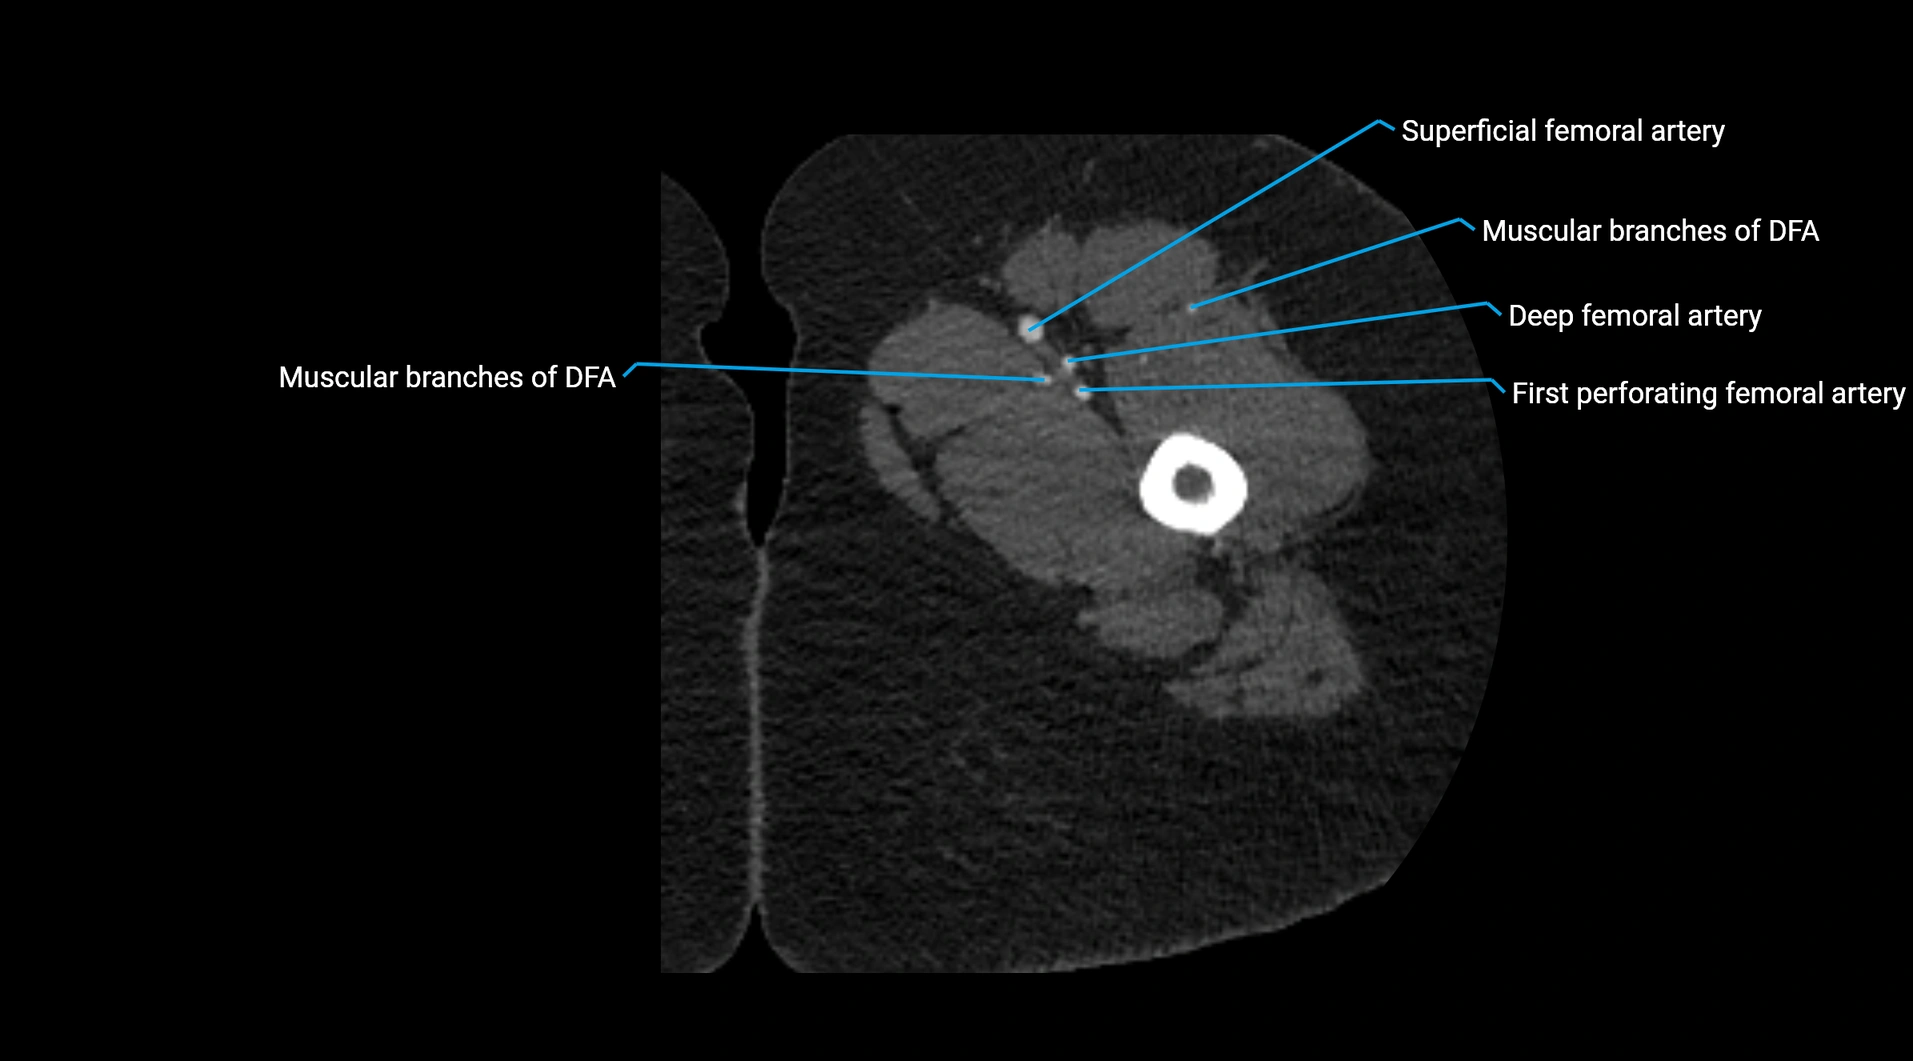

Contrast-enhanced CT (CTA):

• Gold standard for abdominal aortic imaging

• Provides excellent detail of lumen, wall, aneurysm, thrombus, and branch vessels

• Multiplanar and 3D reconstructions help in aneurysm measurement, stent graft planning, and dissection evaluation